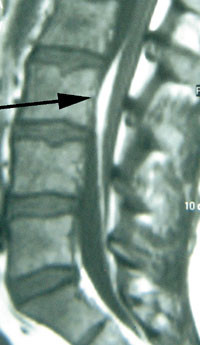

Fortykket filum terminale

Filum terminale er et filament som forbinder enden av ryggmargen (conus medullaris) til halebeinet (os coccygis). Det er normalt tynnere enn 2 mm, men kan være fortykket og inneholde blant annet fettvev eller muskelvev (fig 5). I slike tilfeller kan filum terminale forhindre den normale ascenderingen av ryggmargen som finner sted under barnets lengdevekst, en tilstand kalt kort filum terminale-syndrom.